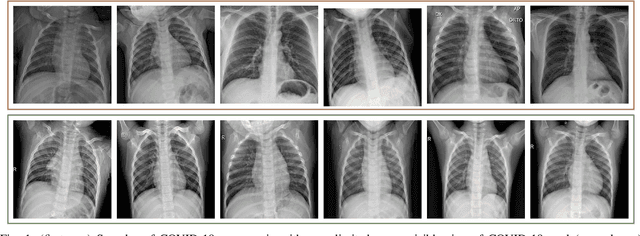

In this study, our first aim is to evaluate the ability of recent state-of-the-art Machine Learning techniques to early detect COVID-19 from plain chest X-ray images. Both compact classifiers and deep learning approaches are considered in this study. Furthermore, we propose a recent compact classifier, Convolutional Support Estimator Network (CSEN) approach for this purpose since it is well-suited for a scarce-data classification task. Finally, this study introduces a new benchmark dataset called Early-QaTa-COV19, which consists of 175 early-stage COVID-19 Pneumonia samples (very limited or no infection signs) labelled by the medical doctors and 1579 samples for control (normal) class. A detailed set of experiments show that the CSEN achieves the top (over 98.5%) sensitivity with over 96% specificity. Moreover, transfer learning over the deep CheXNet fine-tuned with the augmented data produces the leading performance among other deep networks with 97.14% sensitivity and 99.49% specificity.